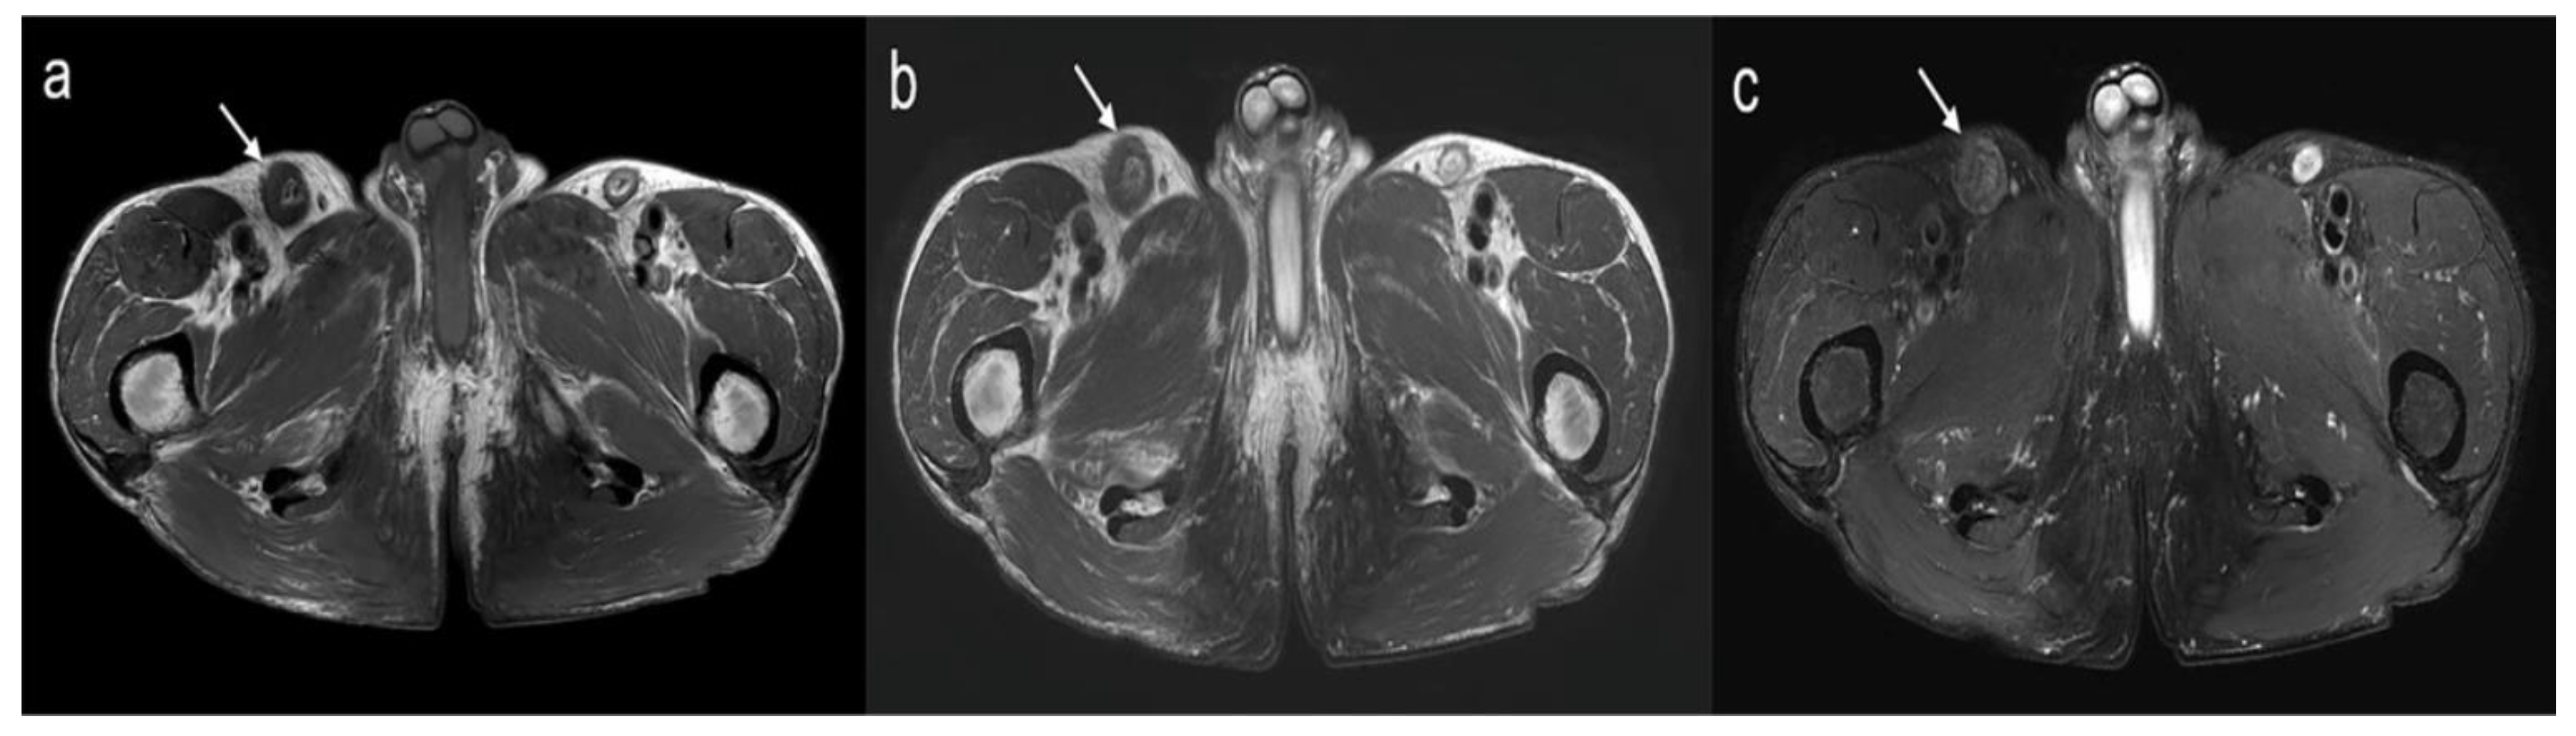

2. Case Report